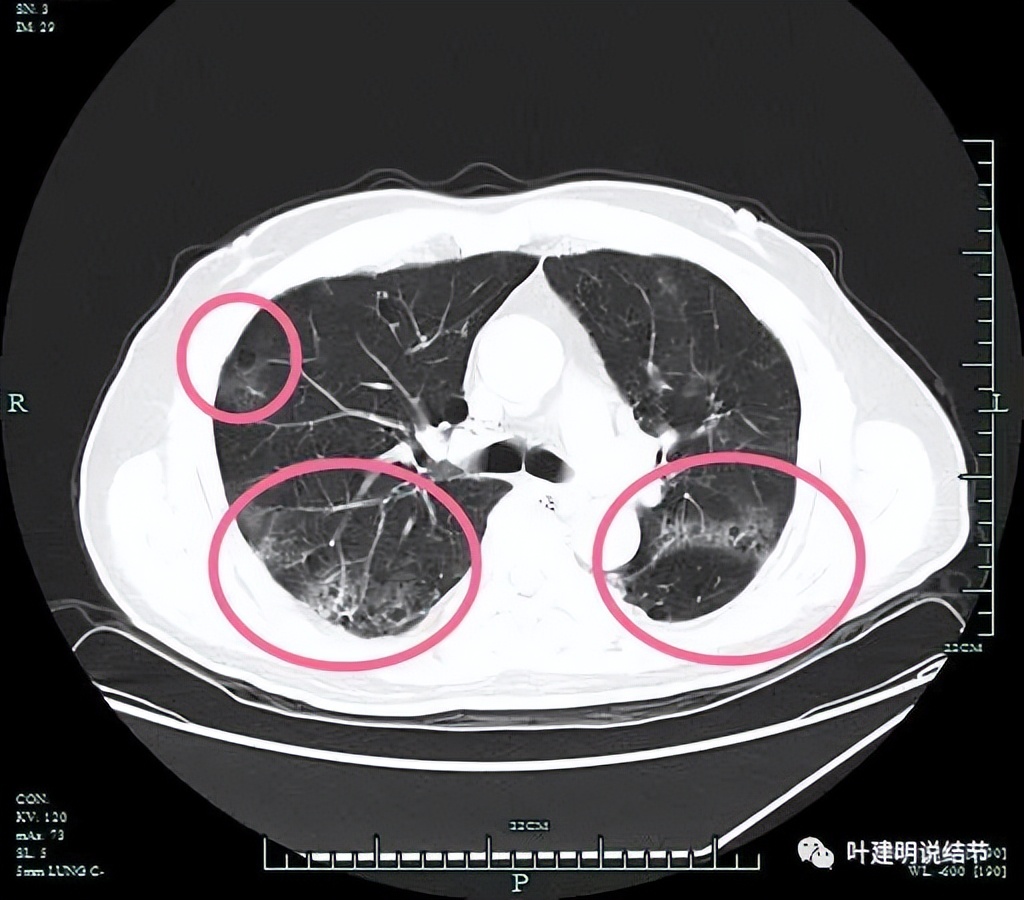

左上病灶开始出现,周围伴慢性炎的表现(红色圈起来部位);其他余部分有多处炎性改变(粉色圈起来的)。

余肺多处间质性炎症或新冠后没有吸收的表现。

上图是非左上病灶层面的多发炎性影像表现(后来考虑是不是与肺门纵嫩淋巴结肿大并葡萄糖代谢相关)。